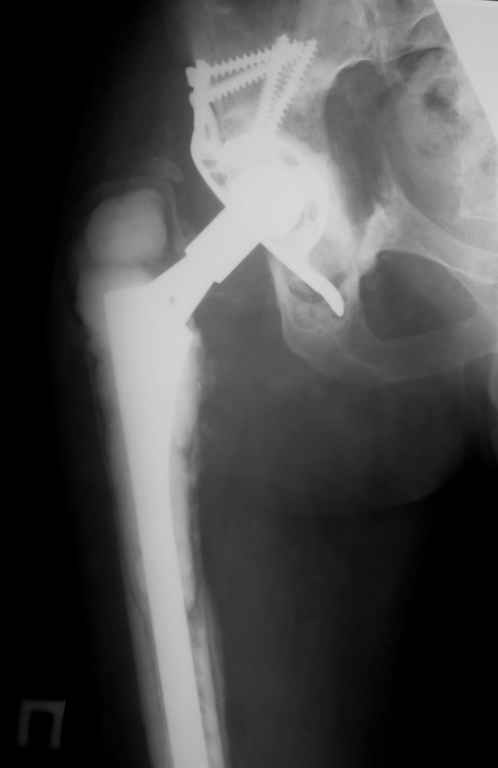

Апрель 2005 |  Декабрь 2005 |  Декабрь 2005 | Реревизия по поводу нестабильности вертлужногокомпонента была выполнена в апреле 2005 г. с пересадкой вертлужной впадины (аллотрансплантат)и защитой трансплантата кольцом Б-Ш.Нагноение выявлено через 6 месяцев, был полностью удален эндопротез (и вертлужный и бедренный компоненты), тщательная ХО мягких тканей с установкой подготовленной из цемента с антибиотиками (родной гентамицин + насыпной ванкомицин) вертлужной впадины опять же на цемент. Установлена новая ножка взамен удаленной на к/цемет с антибиотиками. Рана зажила, б-ая выписана домой. По этой методике прооперировано четверо б-х, пока без рецидива инфекции, одна из пациенток уже поступила для второго этапа.С уважением, Р.Тихилов

Большое спасибо за снимок, теперь все видно! Кстати, по этому поводу: в зоне бедренной кости кортикала осталось очень мало. Планируете ли Вы при окончательной имплантации менять эту ножку на другую (и если да, то на какую именно)?

Мы установили временный протез предназначенный только для движений и ходьбы без нагрузки. "Старый" цемент мы не удаляли поэтому спустя 3-4 месяца планируется выполнить расширенную остеотомию бедра с удалением всего к/цемента и установкой ножки бесцементной фиксации. Обязательным условием является хорошая дистальная фиксация на протяжении минимум 6-8 см. Скорее всего мы используем изогнутую ножку длиной 254 мм, это будет либо ZMR, либо Solution, я еще не планировал этот этап операции.